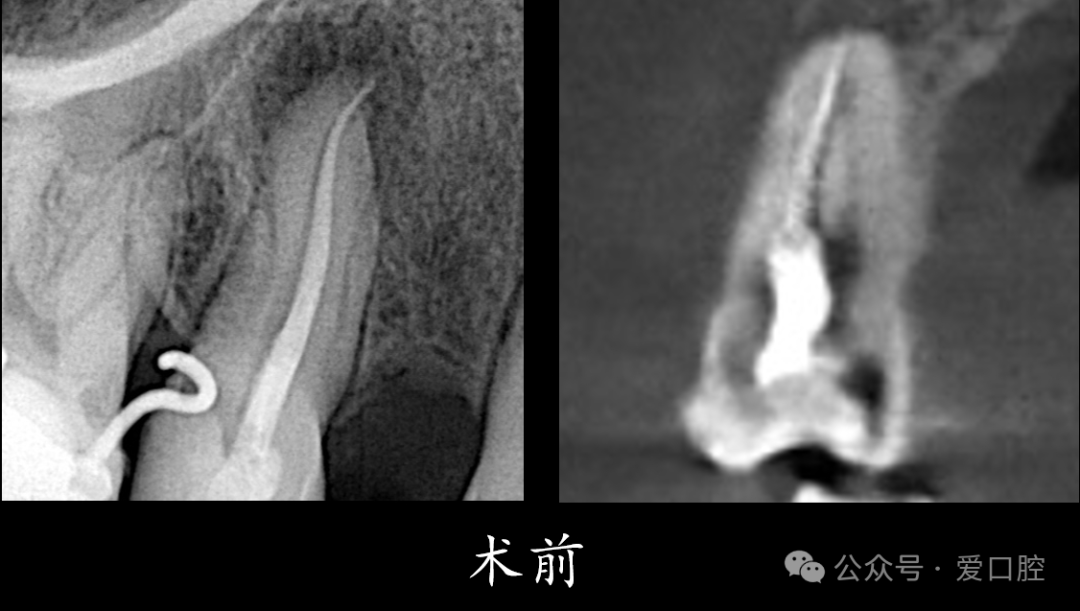

影像学检查:小牙片示:15冠部高密度影,根管内可见高密度影像,牙周膜增宽影,根尖低密度影。CBCT示:15遗漏腭侧根管。

15,安放橡皮障隔离后,显微镜下,开髓,暴露髓腔内牙胶,去除髓腔内牙胶,探查颊侧根管,使用再治疗镍钛锉去除根管上段牙胶,8号k锉,10号k锉疏通至根尖,3%次氯酸钠溶液冲洗,根测长度为19mm,3%次氯酸钠溶液冲洗,探查腭侧根管,发现髓室顶未揭干净,有牙胶残留,揭净髓室顶,去净残留牙胶,疏通腭侧根管至根尖,3%次氯酸钠溶液冲洗,根测长度为19mm,镍钛预备至3504,试尖, 3%次氯酸钠溶液冲洗, Eddy荡洗(20秒3次),蒸馏水冲洗,17%EDTA溶液冲洗,蒸馏水置换,吸干,氢氧化钙封药,玻璃离子暂封。